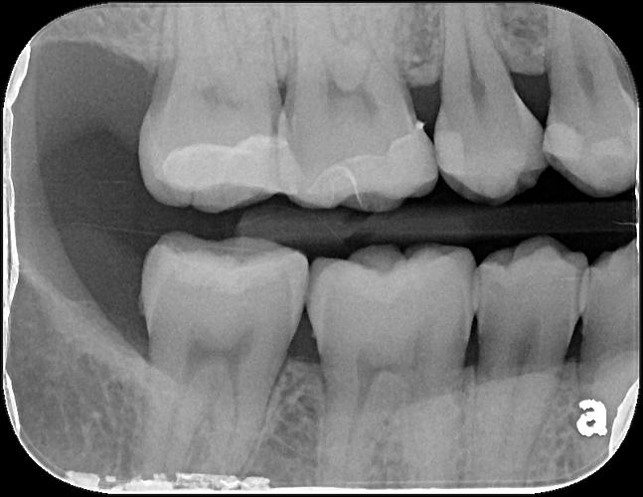

X光可見大臼齒內有蛀洞

治療後,X光密合度良好